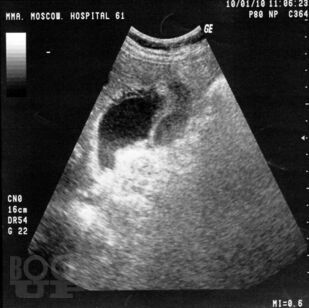

Учебно-методическое пособие посвящено актуальным проблемам этиологии, патогенеза, диагностики, современным методам консервативного и оперативного лечения острого холецистита. Представлены новые классификации, схемы консервативного лечения, современные виды оперативного лечения, учитывая утвержденные клинические рекомендации Российского общества хирургов (2015 г.). Издание иллюстрировано рисунками, таблицами, имеются тестовые задания и задачи. Пособие предназначено слушателей дополнительного профессионального образования и для ординаторов, обучающихся по специальности 31.08.67 Хирургия.